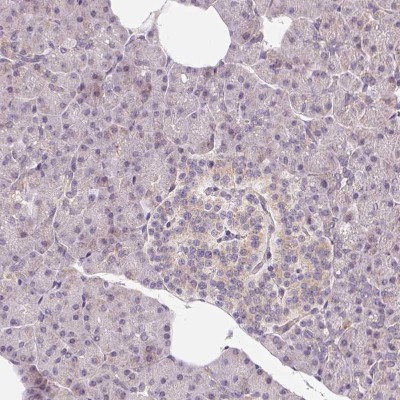

- Immunohistochemistry-Paraffin: OMA1 Antibody [NBP2-30971] - Staining of human lymphoid tissues shows moderate granular cytoplasmic positivity in germinal center cells.

- Immunohistochemistry-Paraffin: OMA1 Antibody [NBP2-30971] - Staining of human pancreas shows low positivity in exocrine glandular cells as expected.